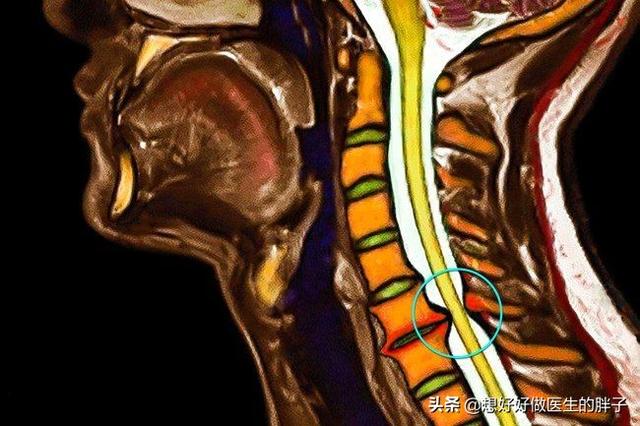

神経根を圧迫する頚椎椎間板ヘルニアは肩の痛みの原因になる

頚椎に鍵盤ヘルニアがあったり、骨髄が形成され圧迫する骨棘がある場合。肩の痛みは、神経根が定位置にない場合に起こる。この痛みの特徴は、電気ショックのようなピンと刺すような痛みがほとんどで、一般的に肩の動きとは無関係である。つまり、この痛みは肩の動きの角度に関係なく存在するということです。むしろ、この痛みと頚椎の活動には関係があるかもしれません。例えば、頚椎を過度に後傾させたり、頭を前に反らせたりすると、神経根が刺激され、痛みが悪化する可能性があります。

簡単に言えば、痛みは肩に現れるが、問題は頸椎にある!

頚椎が肩の痛みを引き起こしていると疑われる場合は、頚椎の検査を行う必要がある。頚椎MRI頚椎椎間板ヘルニアや骨構造の異常が神経拘縮を引き起こしていることを確認し、肩や上肢の筋力低下を伴う場合は、以下のような処置が必要な場合もある。筋電図この検査によって、神経が損傷しているかどうかが明らかになる。治療方法鍼灸を行う、または受けるを達成するために取り組むべき最も重要な問題を以下に挙げる。曳く痛みがひどい場合は経口鎮痛・抗炎症薬このような痛みのほとんどは神経根の浮腫につながるため、内服することが可能である。抗浮腫薬、また、経皮的電気神経刺激などの理学療法を受けることもできますが、通常は体系的な治療で緩和されます。この期間は急性期で1~2週間、徐々に緩和するのに3ヶ月ほどかかりますのでこの種の問題は、物事をゆっくりと進めることが重要なのです。。